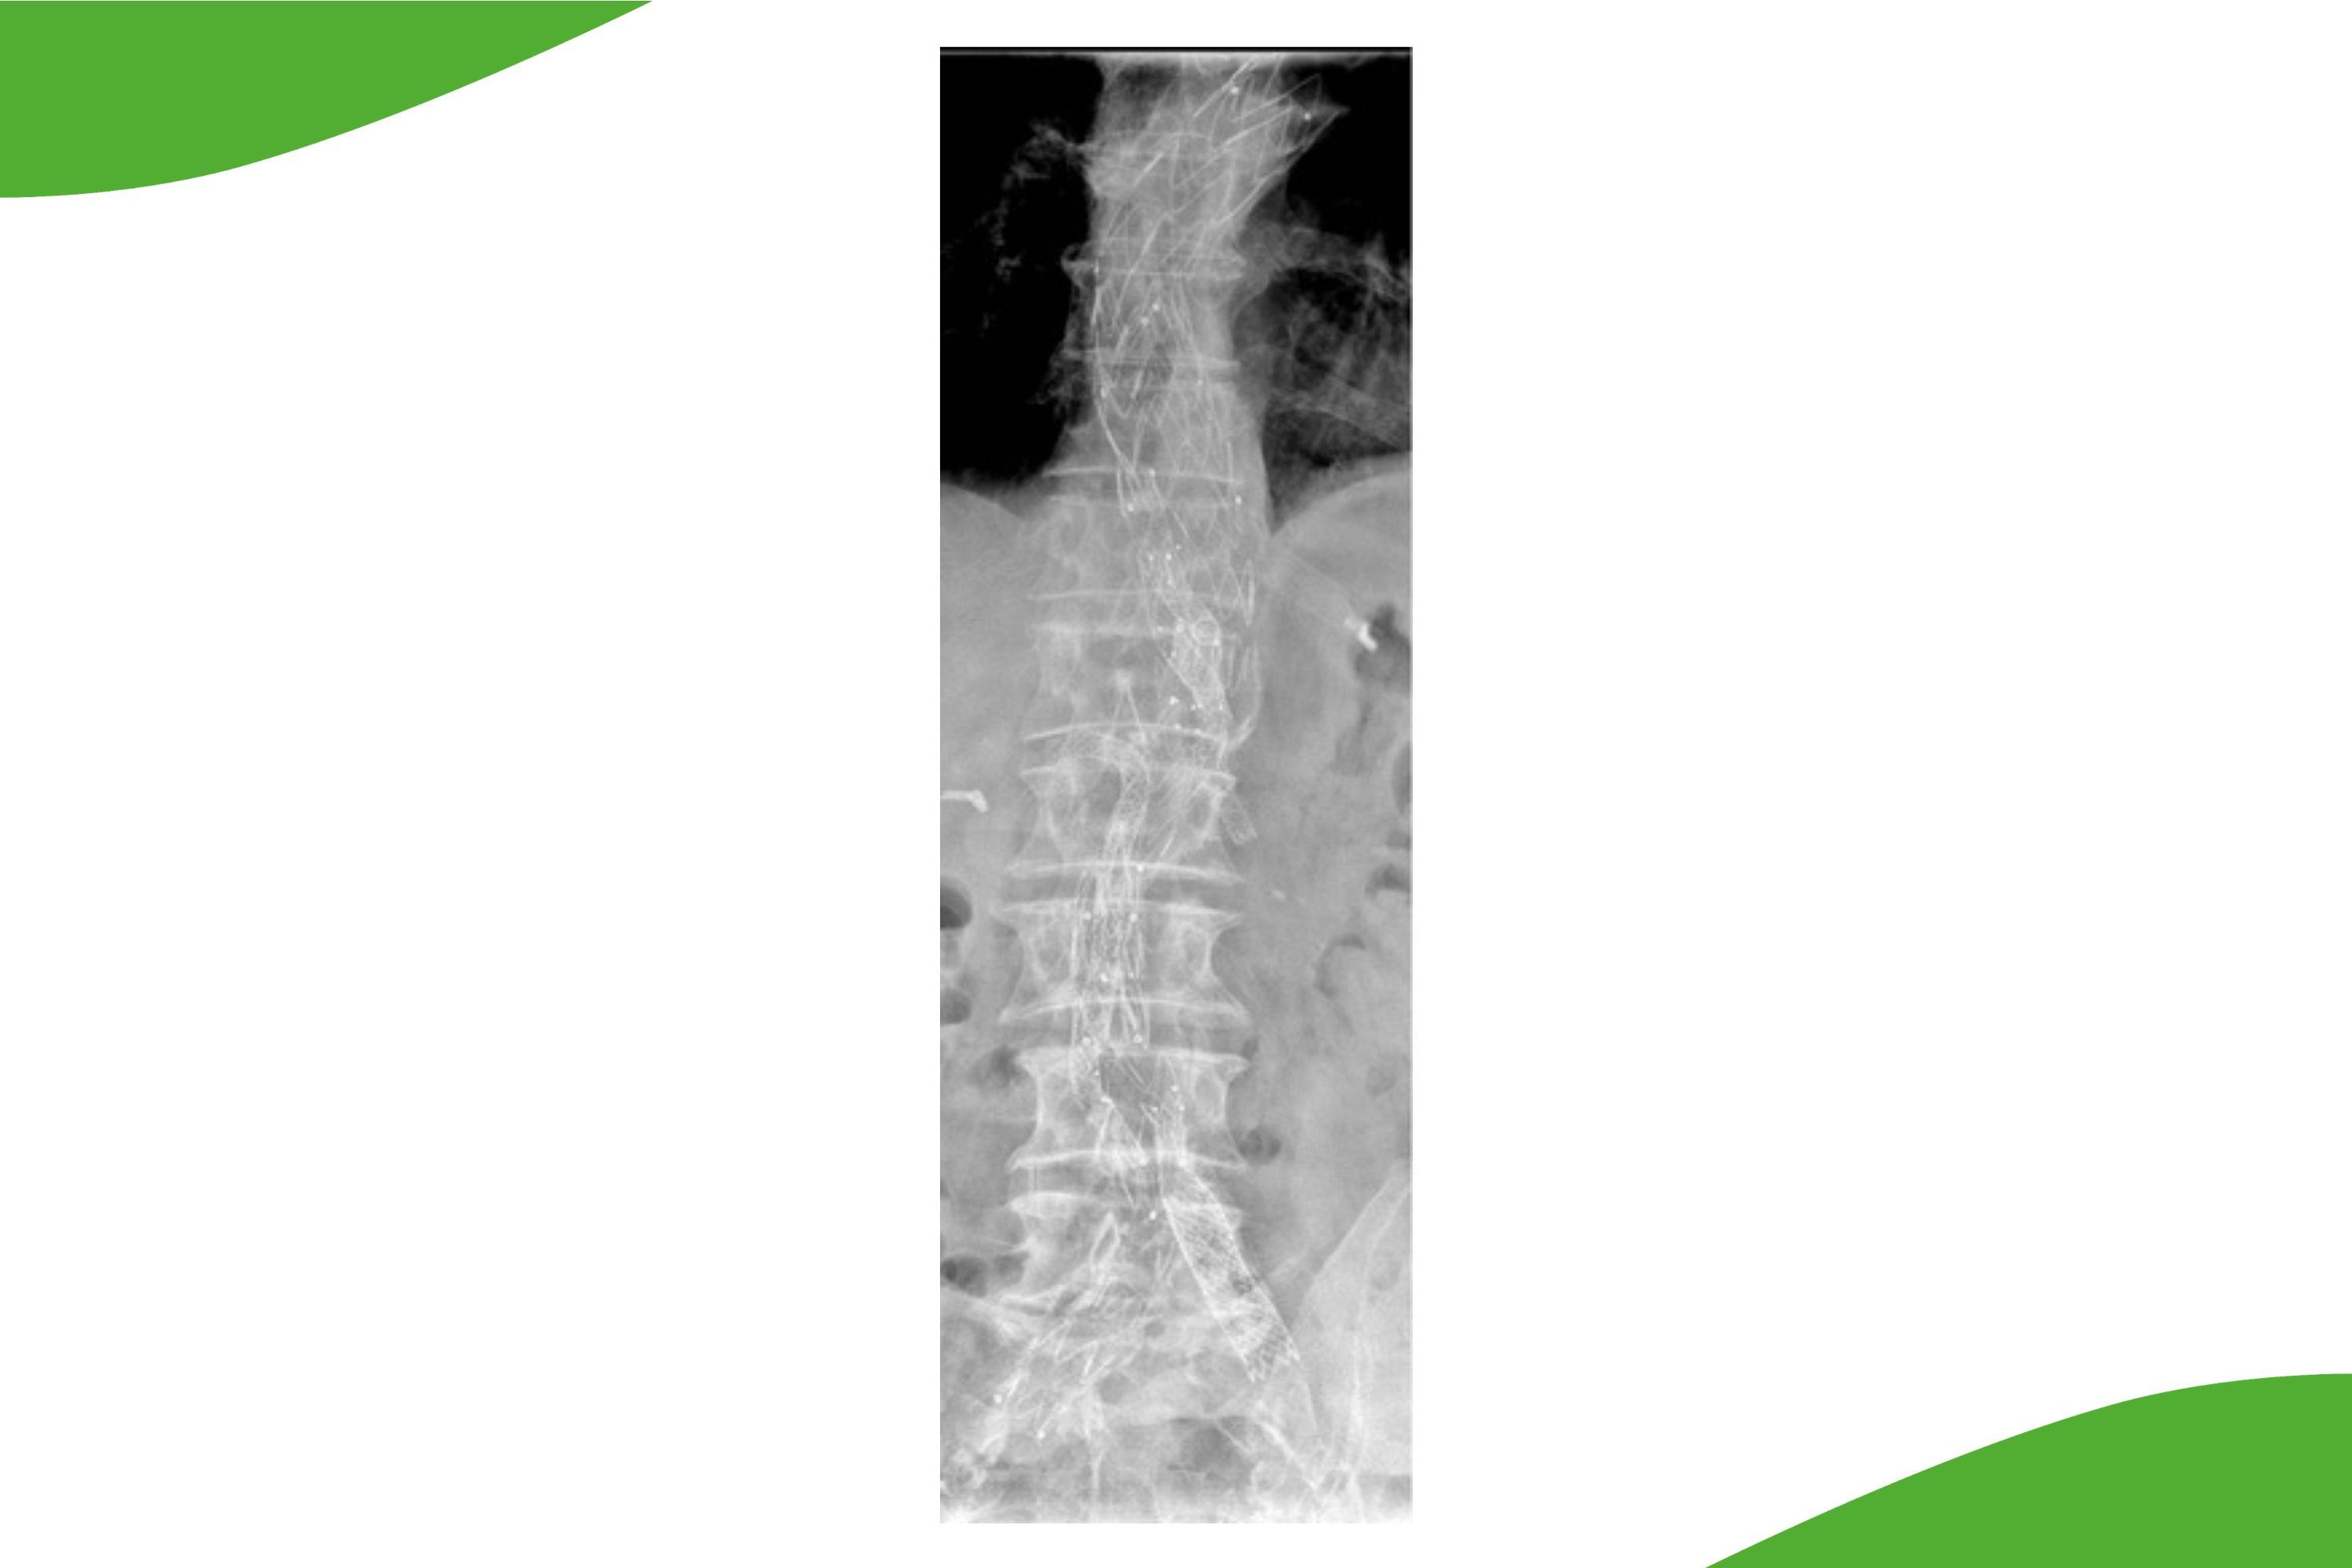

Bei spinalen Blutungen und Gefäßmissbildungen

Im Bereich der Wirbelsäule und des Rückenmarks können Gefäßmissbildungen zu einer Druckschädigung des Rückenmarks oder zu Blutungen führen. Oft können diese feinsten Gefäßveränderungen nur mit einer speziellen Angiographie der kleinsten Rückenmarksgefäße dargestellt werden.